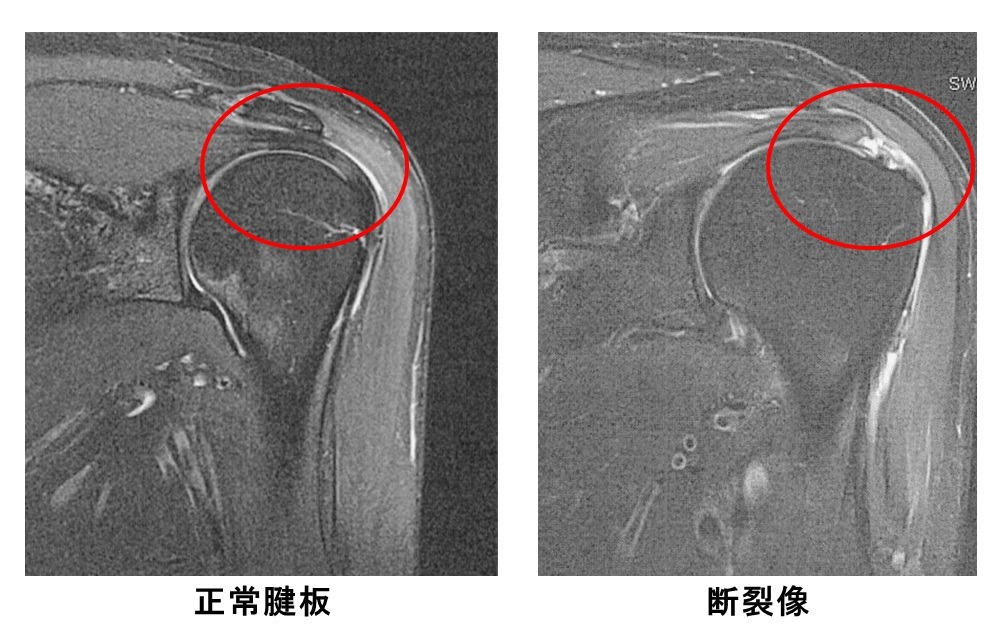

正常腱板と断裂像

加齢および繰り返す機械刺激、外傷を原因として腱板の腱線維が断裂した状態です。40歳以上の男性で右肩に好発、発症年齢のピークは60歳加齢変化で断裂を生じます。60歳で4分の1が、70歳で半数が断裂との報告もあります。断裂しても症状がない人もいますが、夜間痛、動作時の痛みなど、症状がみられたら治療が必要になります。

MRIでの評価と分類